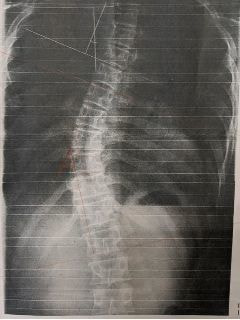

レントゲンのビフォーアフター)

写真1(施術前) 写真2(5か月後)

○コブ角上27度⇒25度(2度改善)、下40度⇒33度(7度改善)

※コブ角は専門医の診断